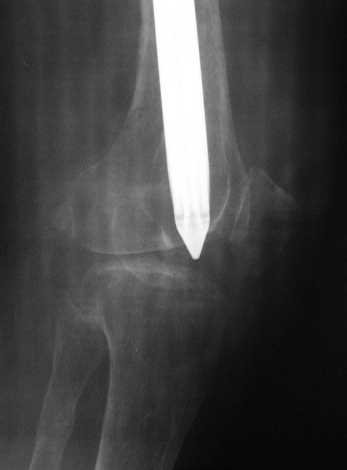

По просьбе коллег выношу на обсужение следущий случай лечения перелома бедра,

рефрактура и фиксация гвоздем "фикшн". Через 2 мес. после синтеза - свищ, "функционирующий"

Правда, что делать с отверстием в колено, вернее как провести санацию так чтобы

минимизировать риск распространения инфекции в коленный сустав, представляется не очень

четко. Необходимую для обсуждения дополнительную информацию предоставлю по мере